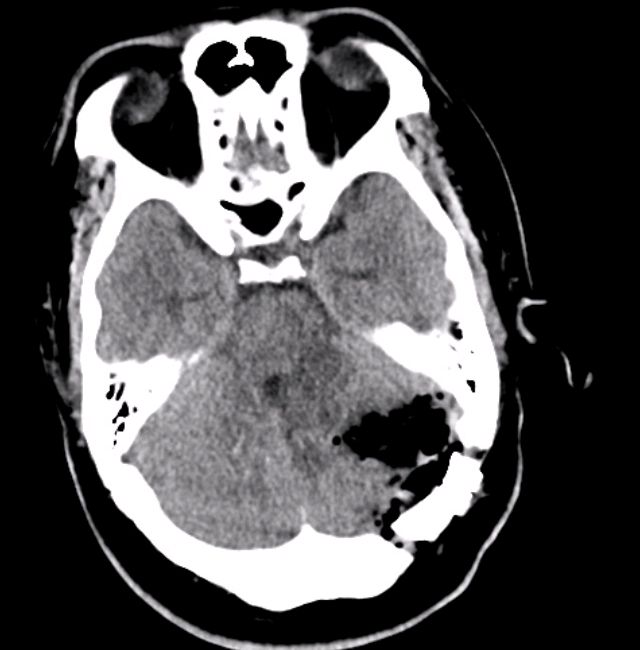

靠近小脑和脑干,紧贴延髓的巨大血管母细胞瘤

小脑血管母细胞瘤